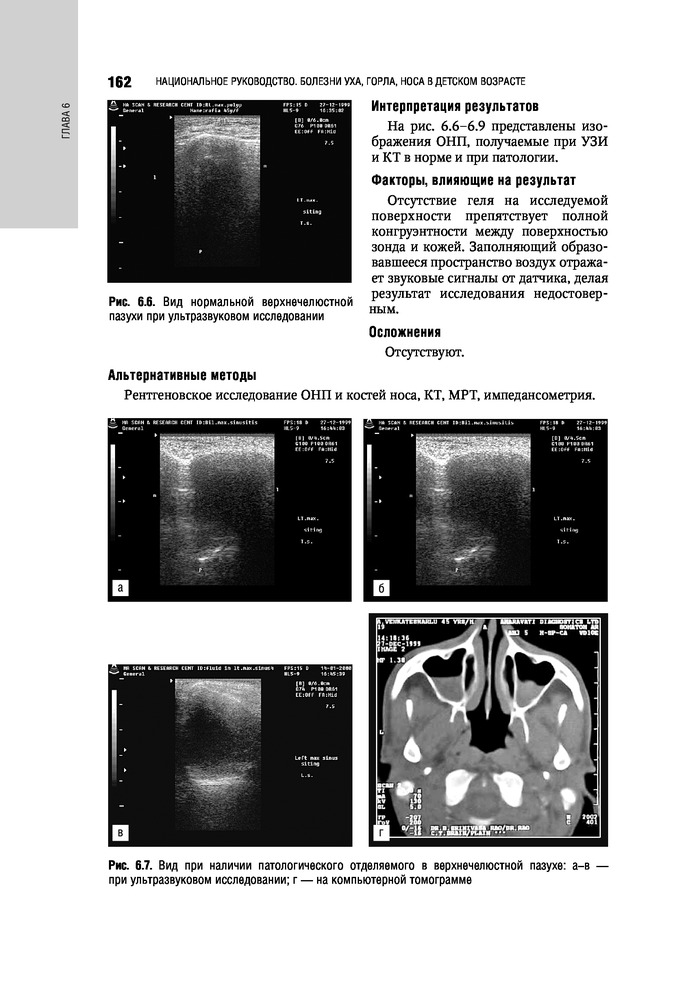

%text%